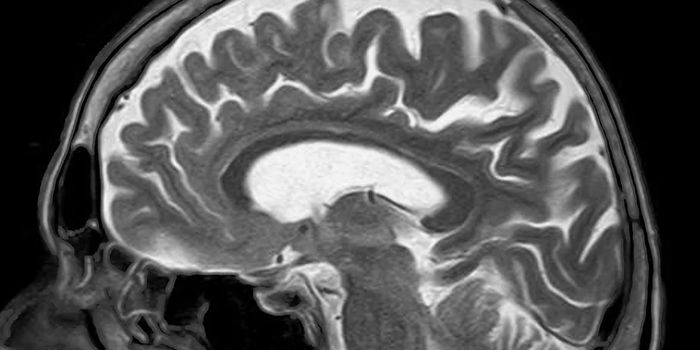

Read the latest articles about newly released neuroscience research and advances in experimental techniques. Topics include research news in neuroscience, neurology, psychology, brain science and cognitive sciences.